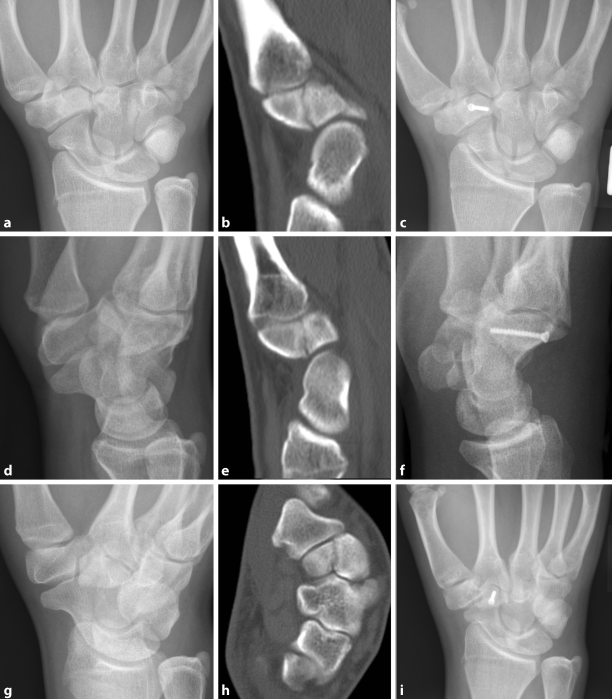

Behandlung Von Handwurzelfrakturen

Frakturen Der Handwurzelkno Chen Springerlink